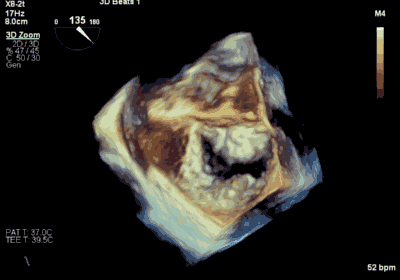

▲ MitraClip释放

患者全麻以后,在经食道超声心动图和X射线引导下,经股静脉入路,将MitraClip瓣膜夹顺利送至二尖瓣前后叶交界中心处,成功捕捉二尖瓣前叶A2和后叶P2,经超声心动图反复确认瓣叶夹持牢固后,测定有效夹持长度10.4mm,评估反流量降至轻度,释放瓣膜夹,超声心动图评估瓣膜夹位置和功能良好,测定左房压降至26/12mmHg,再次评估反流量仍为轻度,手术顺利完成。

王焱、王斌教授团队通过术前和台北荣民总医院(Taipei Veterans General Hospital)宋思贤教授进行了详细的讨论并制定了最优的手术策略,同时术中视频连线获得宋思贤教授的技术支持,爱情岛论坛 超声内科苏茂龙教授负责术中超声心动图引导。患者全麻以后,在经食道超声心动图和X射线引导下,经股静脉入路,将MitraClip瓣膜夹顺利送至二尖瓣前后叶交界中心处,成功捕捉二尖瓣前叶A2和后叶P2,经超声心动图反复确认瓣叶夹持牢固后,测定有效夹持长度11mm,评估反流量降至微量,释放瓣膜夹,超声心动图评估瓣膜夹位置和功能良好,测定左房压降至11/6mmHg,再次评估反流量仍为微量,手术顺利完成。